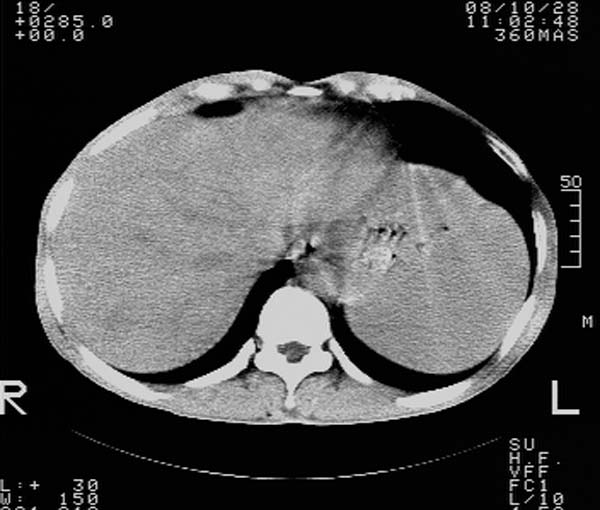

m,65y。半年前发现颈小结节,逐渐增多增大,现双侧耳后、颌下及颈部表浅淋巴肿大。胸片示双肺门增大。外院曾穿刺诊断为淋巴结核。在我科作胸腹部ct,我们觉得外院病检有误。现将图像上传请战友讨论。

纵隔内及腹膜后广泛淋巴结肿大,脾大,肝内似可见低密度影,结合病史半年前发现颈小结节,逐渐增多增大,现双侧耳后、颌下及颈部表浅淋巴肿大。考虑淋巴瘤。

我们也是首先考虑淋巴瘤。只是外院病检报告是结核。让人迷惑。肝左叶多发低密度占位,没增强不好定论。

纵隔,双肺门腹膜后多发淋巴结重大,非融合,肝脾轻度肿大,双肺野弥漫性小结节;考虑淋巴瘤,结节病可能性

纵隔内,双肺门、腋窝及腹膜后多发肿大淋巴结影,肺内小结节影,肝脾体积增大,支持淋巴瘤。肝内多发低密度影,考虑小囊肿。

考虑淋巴瘤肺、肝内转移,脾脏肿大。

纵隔内,双肺门、腹膜后多发肿大淋巴结影及颈部淋巴结肿大,肝脾体积大.结合临床,淋巴瘤可能性大。